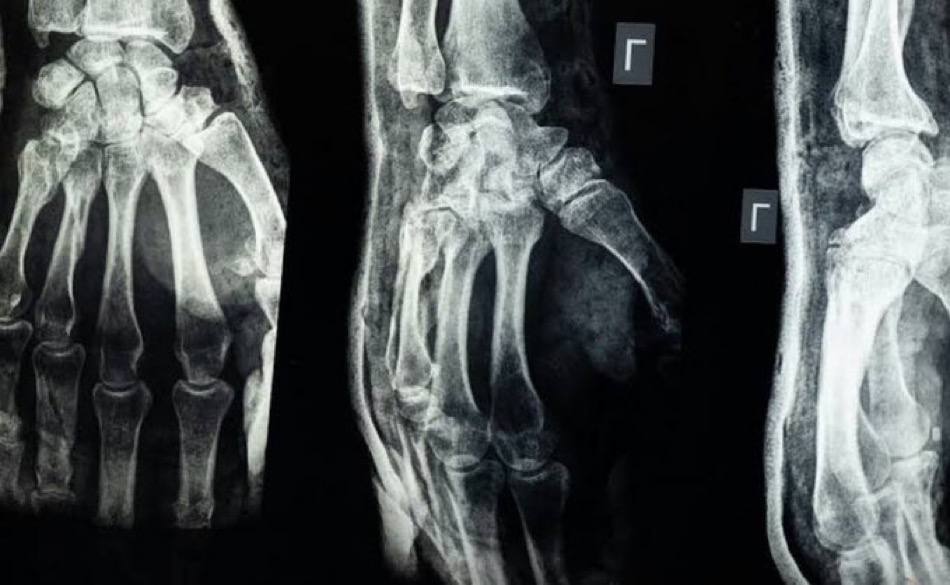

Биологический материал, вдохновленный устрицами, может изменить ортопедическую хирургию.

Китайские исследователи создали уникальный медицинский клей, способный соединять сломанные кости в считанные минуты.